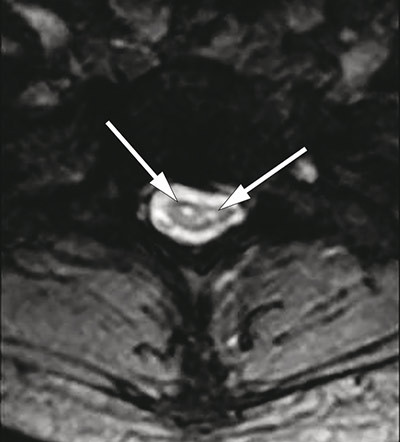

MRI of the spinal cord showed marked atrophy from C4 to Th2 and two longitudinal symmetrical T2-weighted hyperintense lesions from C2 to Th2 (<<<. 3, Fig. 4), confined to the anterior horn area of the medulla. The changes were not considered consistent with syringomyelia, demyelinating plaques, tumour or transverse myelitis. MRI of the head was normal.

Figure 3  Sagittal T2-weighted cervical MRI with atrophy of the medulla from C6 to Th2 and hyperintense lesion from C4 to Th2